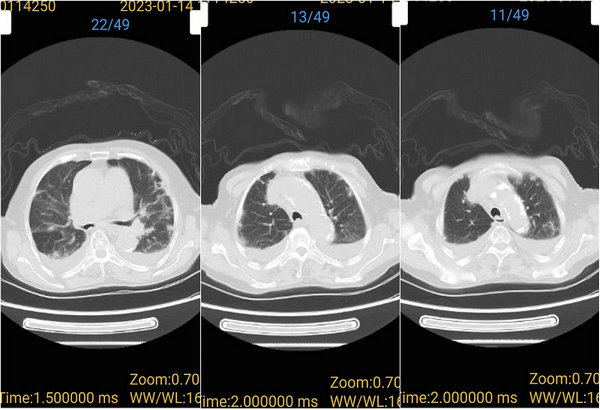

治疗后肺部CT显示明显好转

经过几天的对症治疗,曹奶奶意识逐渐恢复,无面罩吸氧时血氧饱和度已达到90%以上,也有了食欲,可以正常进食,病情也随之奇迹般地好转起来。如今,曹奶奶的核酸转阴,在家人的搀扶下也能下地走路了。